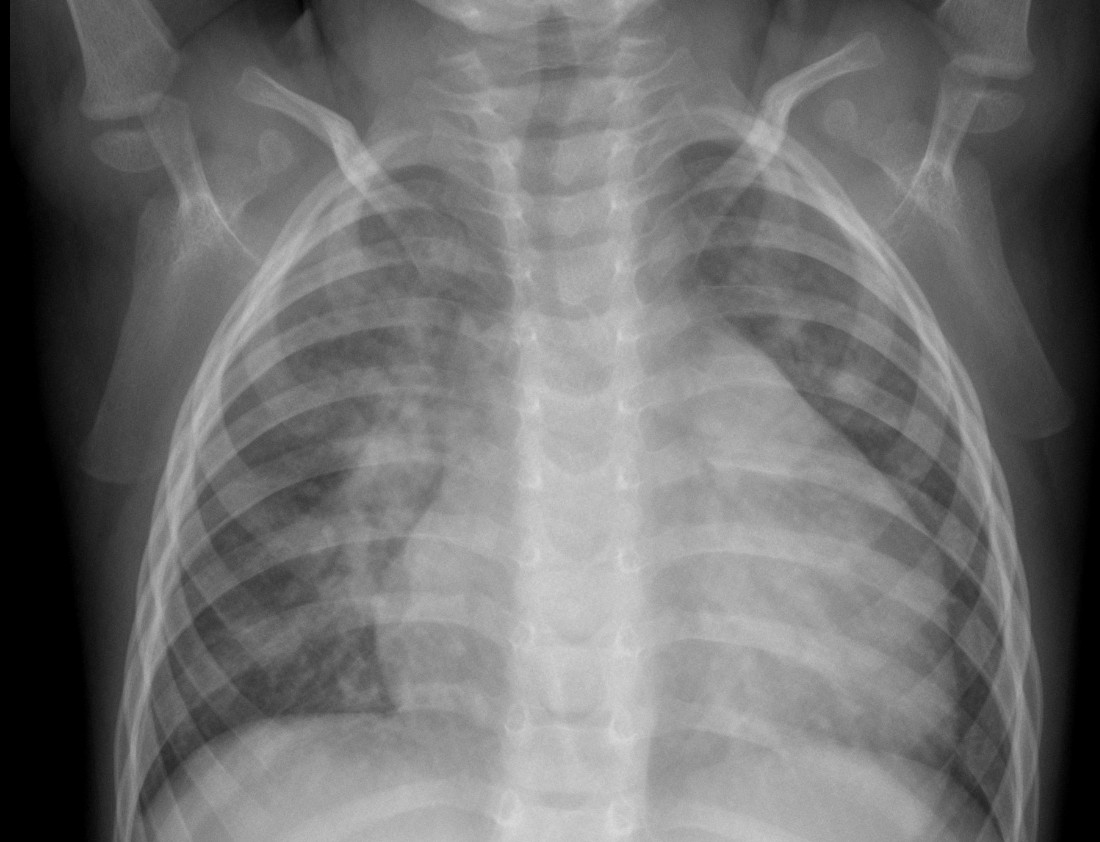

CASO: Niño con sensación disnéica que ha ido incrementado en la última semana.

Hallazgos:

- Se observa un ensanchamiento mediastínico a expensas de una masa que desciende el hemidiafragma y borra el borde derecho del corazón.

- En la placa lateral se observa la posición de la masa en posición anterior.

¿ES UNA MASA MEDIASTÍNICA?

Cuando se observa una masa en la placa de tórax, es posible que se localice en el mediastino. Para saber si es una masa mediastínica aquí tenemos unos objetivos a analizar:

- ¿Es una masa mediastínica?

- ¿Es anterior, media o posterior?

- ¿Es posible definir si tiene grasa, aire o líquido?

1)- Las siguientes características indican que la lesion se origina en el mediastino:

- Al contraio que en el pulmón, una masa mediastínica no contiene broncograma aéreo.

- Los márgenes con el pulmón son obtusos.

- Las líneas mediastínicas estarán interrumpidas.

- Pueden estar asociadas anormalidasdes espinales, costales o esternales.

2)- El mediastino puede dividirse en anterior, medio y posterior (la separación es virtual, no hay tejido ni plano que separe estos tres compartimentos). Esta división nos será util a la hora de realizar los diferentes diagnósticos diferenciales.

- En la placa lateral el compartimento anterior y medio se separa dibujando una línea imaginaria anterior a la tráquea y posterior a la vena cava.

- El compartimento medio y posterior se separan dibujando una línea imaginaria que pasa 1cm posterior al borde anterior de los cuerpos vertebrales.